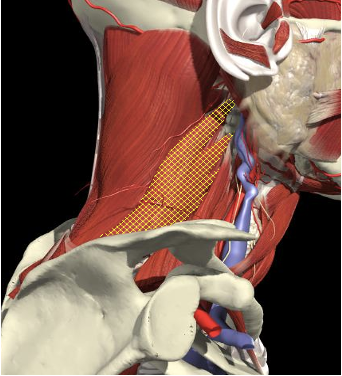

The Interscalene Groove

- The interscalene groove lies immediately behind the lateral border of the clavicular head of the sternocleidomastoid muscle at the level of the cricoid cartilage (C6)

- Approximately 1cm above the separation of the sternal and clavicular heads of the sternocleidomastoid muscle.

Brachial Plexus

The BP lies inferior to a line from the posterior margin of the sternomastoid at the level of the cricoid cartilage to the midpoint of the clavicle

Structures to Avoid

The BP lies inferior to a line from the posterior margin of the sternomastoid at the level of the cricoid cartilage to the midpoint of the clavicle. Scalenus medius is behind and above line.

Interscalene Groove & Brachial Plexus

Interscalene groove